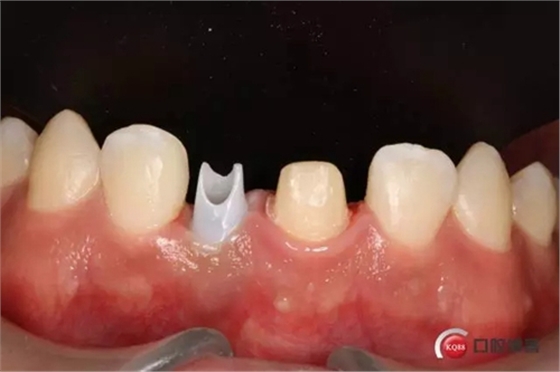

種植后修復,我們要把握每一個細節(jié),比色,轉(zhuǎn)移桿的就位,我們必須把臨床做好,技工師傅才會給我們做出好的修復體,減少一些不必要的失誤,首先術前的檢查是必要一步 ,再是器械的準備使我們臨床操作有條不紊,術前拍照,o-bite取咬合記錄,消毒修復術區(qū),旋出愈合基臺,生理鹽水沖洗袖口,拍照袖口,安放合適轉(zhuǎn)移桿,拍X線見轉(zhuǎn)移桿就為良好,硅橡膠取模,術后旋回愈合基臺,拍照比色。

藻酸鹽對頜取模,超硬石膏灌注。發(fā)加工廠,與技工溝通注意事項,等修復體做好后,檢查模型。是否就位,是否密合,預約患者復診戴牙,消毒修復區(qū),旋出愈合基臺,定位器指導安放修復基臺,試戴冠,調(diào)磨鄰接及 咬合至合適,拋光,患者滿意,加力扳手加力至30N,拍X片見就位良好,特芙蓉及暫封膏封中央螺絲孔,聚羧酸鋅粘固劑粘固,或是樹脂水門汀粘固,清理多余粘結(jié)劑,光固化樹脂封螺絲孔,拋光。術后注意隨訪。